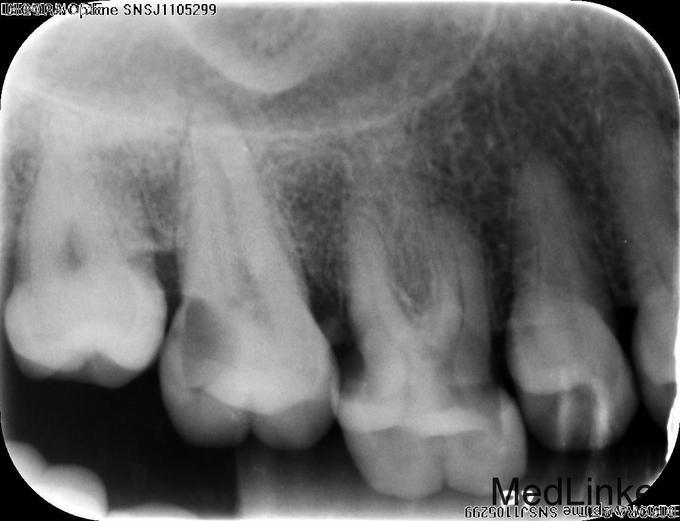

主诉:右上后牙反复食物嵌塞数年,疼痛3月 现病史:患者自述右上后牙进食时反复发生食物嵌塞,近三月嵌塞现象明显,并伴有疼痛,进食食物嵌塞时疼痛明显,偶尔伴有剧烈疼痛,于我院就诊,要求治疗。 既往史:否认牙科治疗时,否认全身系统疾病史及药物过敏史

检查:#17和#18间,#17和#16间,#16和#15间食物嵌塞,探及龋损,于#17远中和#16近中尤为明显,深探时引起患者不适,但无剧烈疼痛,换牙无松动,患牙冷诊发生疼痛,并持续数十秒,#17远中和#16远中谈及深牙周袋,探诊出血。 对合牙尖高耸。 x-ray示#17远中,#16近中深龋损,近牙髓。

诊断:#17、#16慢性牙髓炎 治疗: 调磨对合尖锐牙尖 #17、#16碧兰麻下开髓,封三甲+OC球,ZOE暂封; 2周后复诊去暂封,清理髓腔及根管,双氧水和生理盐水交替冲洗清空根管,分别测WL,手动+镍钛锉预备各根管,拍片试尖达工作长度,根管内导入糊剂,侧压充填中下段,热牙胶充填上段,X线示恰填,GIC暂封。转诊修复科行冠修复。并行系统牙周治疗,拔除智齿。